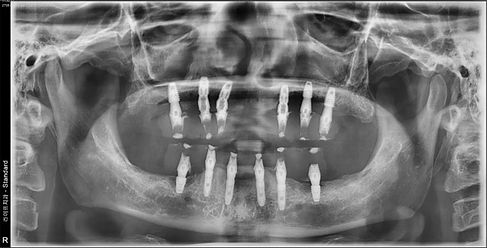

전체 임플란트는 심한 치주질환이나 외상, 충치 등의 다양한 이유로 모든 치아가 상실된 경우 14 개 정도의 임플란트를

식립하여 상실된 치아 기능을 회복시키는 시술입니다.

전체 임플란트는 심한 치주질환이나 외상, 충치 등의 다양한 이유로 모든 치아가 상실된

경우 14 개 정도의 임플란트를 식립하여 상실된 치아 기능을 회복시키는 시술입니다.